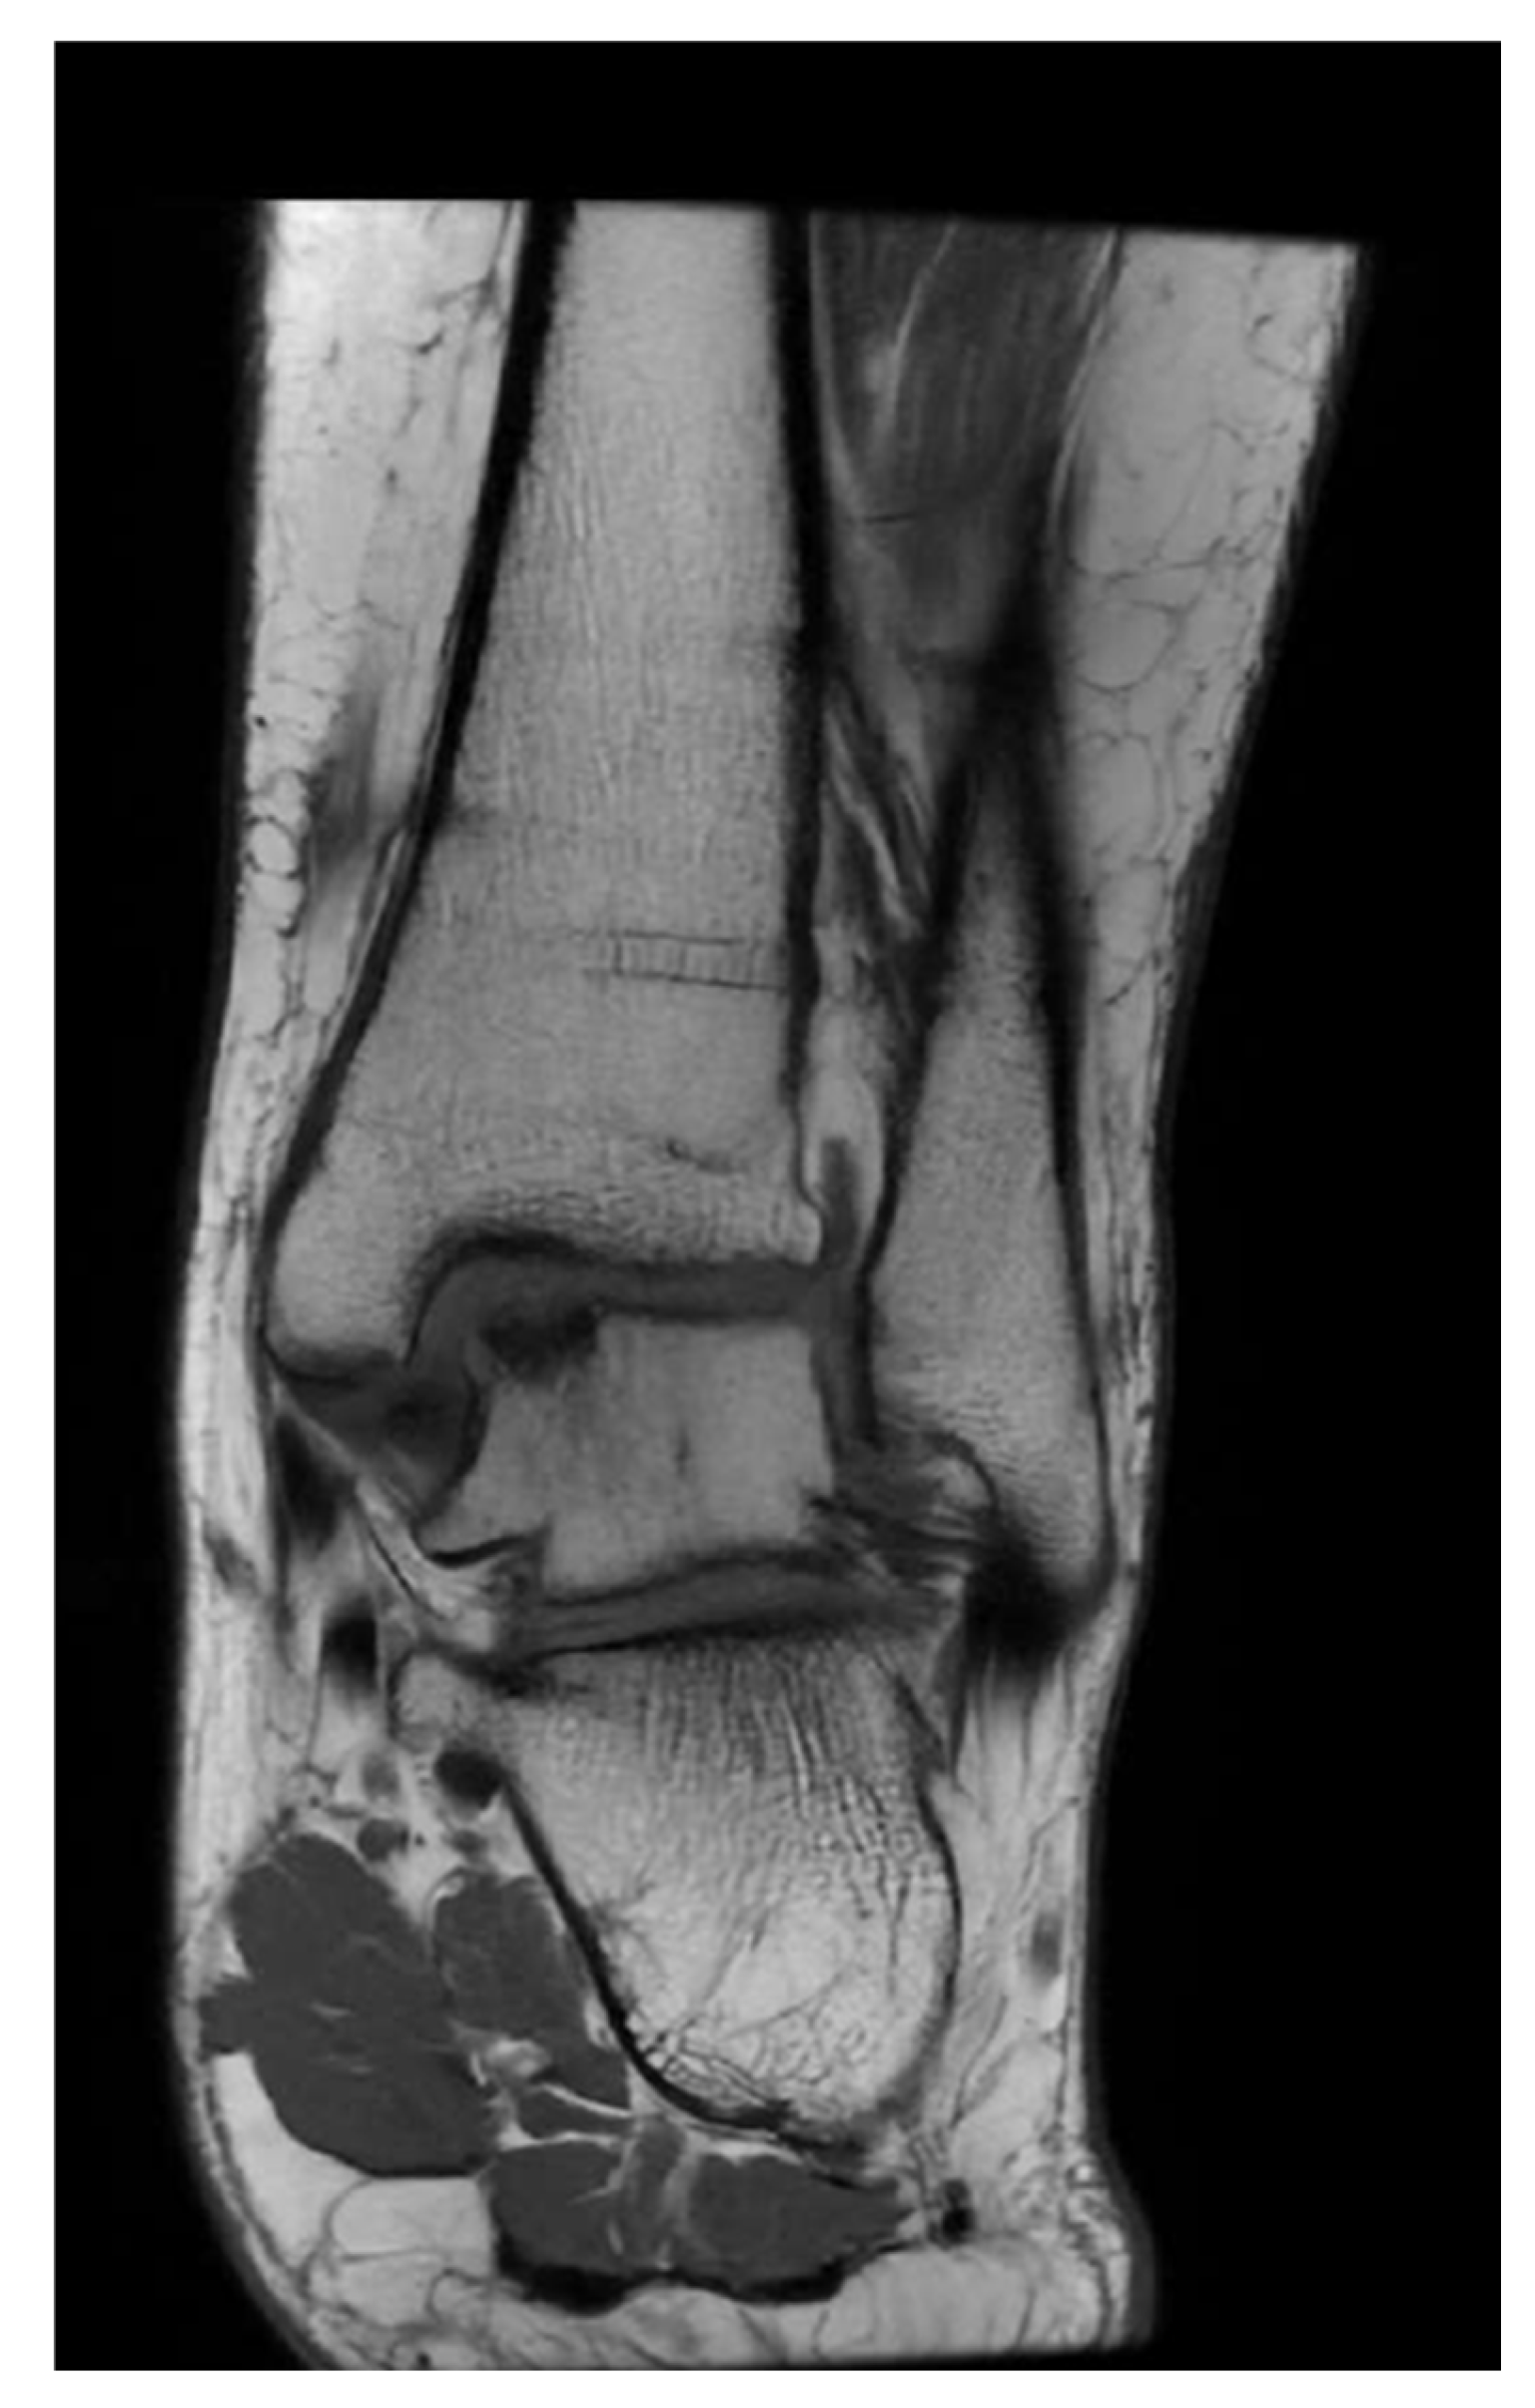

2.3. Radiological Assessment